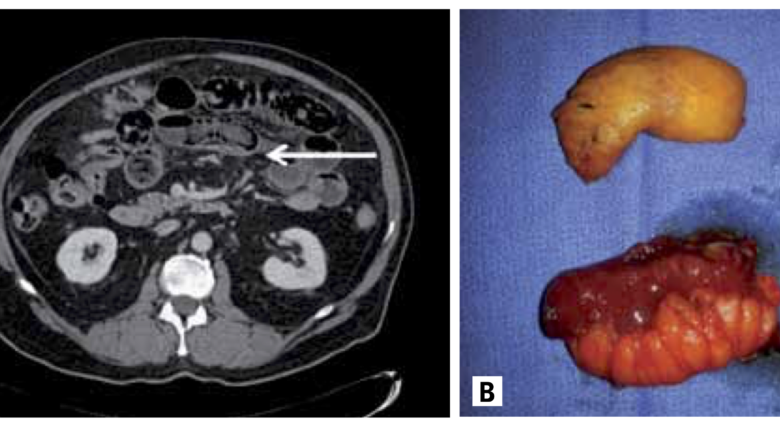

Une équipe de l’hôpital Beth Israël de New York a rapporté le cas d’un Bezoar causé par l’ingestion  de matzots à Pessa’h ( Sastry A, […]